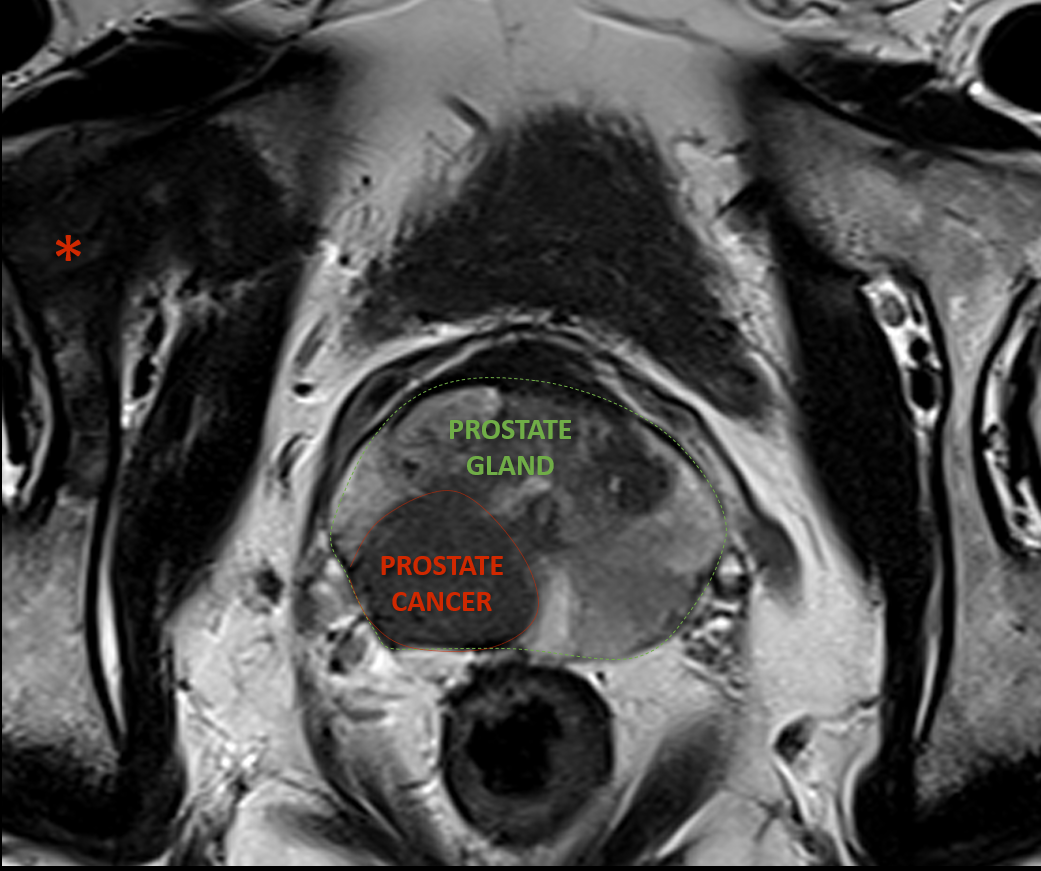

④ 전립선 조직검사

암이 의심될 경우 시행합니다.